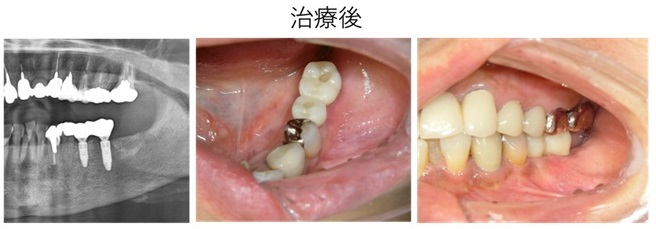

症例① 歯根破折のため左臼歯部を抜歯しインプラント治療を行なった治療例。